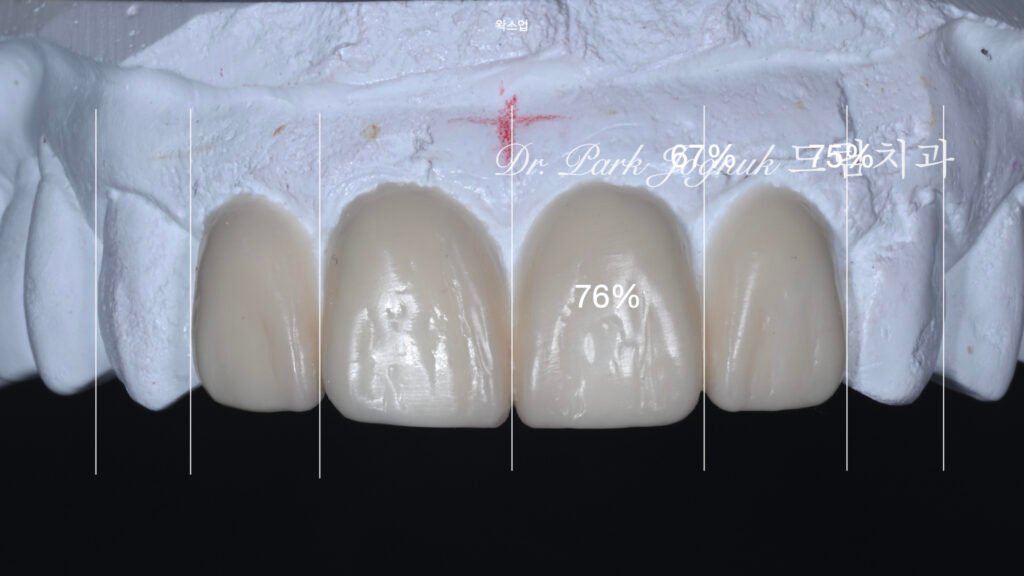

왁스업 재설계: 이상적 형태의 구현

사진 3은 왁스업 정밀진단(Diagnostic wax-up) 결과입니다. 모든 문제점을 해결하는 종합적 재설계입니다.

크기 최적화

환자의 안면 특성에 어울리는 이상적인 치아 크기를 설정했습니다. 과도하지도 작지도 않은, 자연스러운 비율을 구현했습니다.

형태 재설계

해부학적 형태 구현: 각 치아에 자연스러운 발육엽, 표면 굴곡, 미세 텍스처를 설계했습니다.

의도적 불완전성(Intentional imperfection): 완벽한 대칭이나 매끄러움이 아니라, 자연치아의 미묘한 불규칙성을 의도적으로 포함시켰습니다.

개성 부여: 각 치아가 고유한 특성을 가지면서도 전체적으로 조화를 이루도록 설계했습니다.

대칭성 확립

좌우 중절치를 완벽하게 대칭적으로 설계하여 심미적 균형을 확립했습니다.

표면 특성 계획

발육엽, 미세 균열선(Craze line), 표면 불규칙성 등 자연치아의 모든 특성을 계획했습니다.

환자분께서 왁스업 모형을 보시고 “이제야 제대로 된 치료를 받는 것 같다”며 신뢰를 표현하셨습니다.